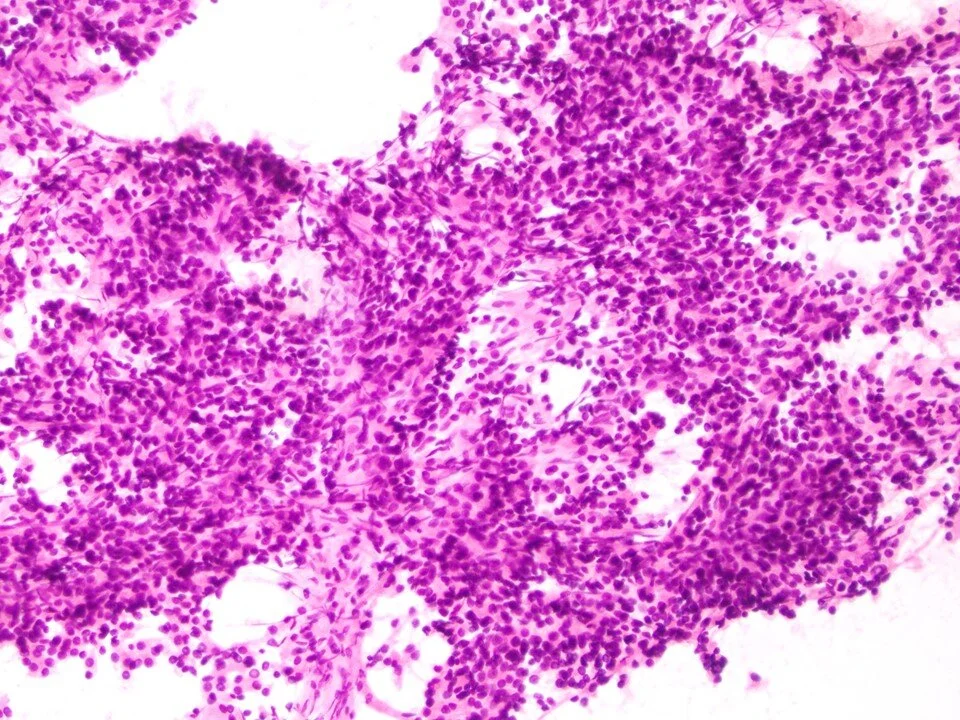

Small cell carcinoma